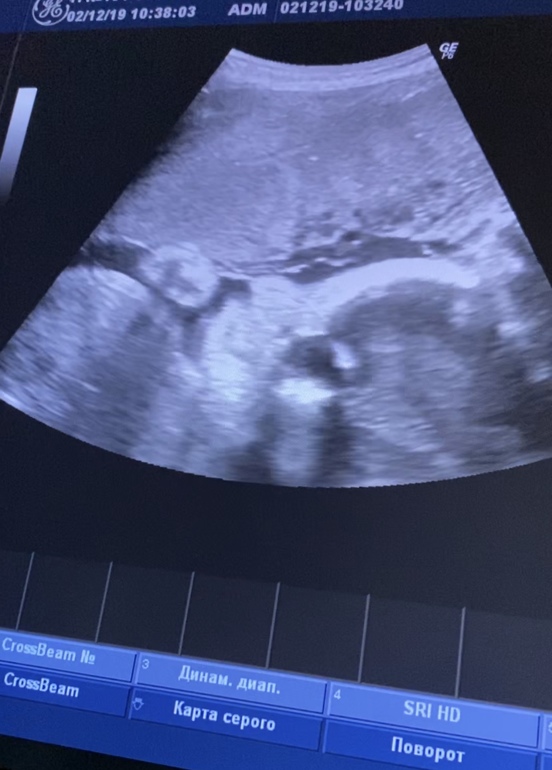

Узи 28 недель

Всё о нашей беременностиВот и прошло мое крайнее узи перед декретным отпуском. Уже пролетело 28 недель. До встречи осталось не долго. Нам наконец-то подтвердили пол уже все хорошенько видно 🤣 ждём девочек 👧🏼 Захотелось пойти накупить бантиков 😂 По показателям все отлично. Шейка 38, малышки по 1200 грамм. Но вот нижняя уселась на попку. Теперь переживаю успеет ли перевернуться. Буду надеяться на лучшее. Впереди самое сложное: выбор имён 😂 Совсем не верится, что осталось так мало времени, так хочется подольше насладиться этим положением (надеюсь мнение не изменится 🤣). Ну и напоследок мои курносики ❤️